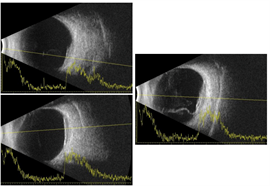

Optical coherence tomography through the macula of the right eye demonstrated a clear vitreous, normal retinal laminations, and mild irregularity of the retinal pigment epithelium band within the fovea. There was no intraretinal or subretinal fluid. There was thickening and consolidation of the submacular choroid with hyporeflective lamellae within the lesion and no normal choroidal vasculature visible in this area. B-scan ultrasonography demonstrated a plaque-like, hyperechoic choroidal lesion with shadowing posterior to the lesion.

Spectral-domain optical coherence tomography (OCT) showed choroidal elevations with subretinal fluid OD and large choroidal elevation with intraretinal and subretinal fluid OS (Figure 2). Fluorescein angiography (FA) demonstrated two circumscribed areas of punctate hyperfluorescent spots located just above the superior arcade and nasal to the nerve OD and a large circumscribed area of punctate hyperfluorescent spots in the macula with central hypofluorescence OS (Figure 3). A/B scan ultrasonography shows two distinct choroidal hyperechoic lesions with high internal reflectivity in OD with maximal height of 2.90 mm and 2.50 mm and a choroidal hyperechoic lesion with high internal reflectivity with maximal height of 2.97 mm and associated subretinal fluid (Figure 4).